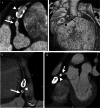

Imaging the coronary arteries of children, with their faster heart rates, small vessel size and common inability to lie still or breath-hold, has been a major challenge. With numerous advances in technology, CT examinations can now be performed quickly, often with children free-breathing and with much lower radiation doses than previously. This has led to increased use in children. Care must be taken with technique and choice of electrocardiogram (ECG)-gating technique to obtain adequate imaging for a diagnosis while keeping radiation dose as low as reasonably achievable (ALARA). In this paper, we discuss techniques and tips for CT imaging of the coronary arteries in children, including use of dual-source- and ultrawide-detector CT scanners.